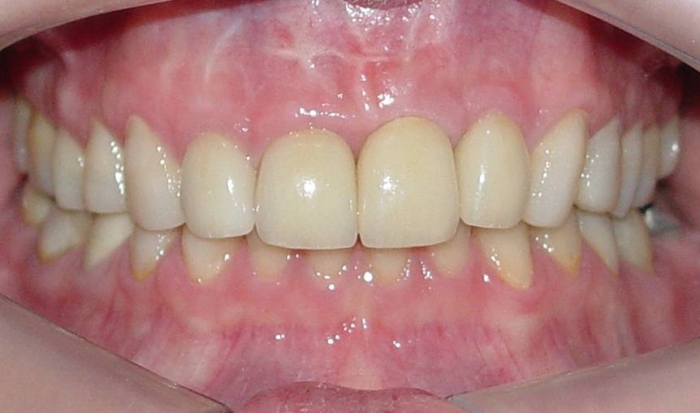

Prótese fixa de porcelana sobre o implante

Sorriso final do caso terminado em Dezembro de 2011